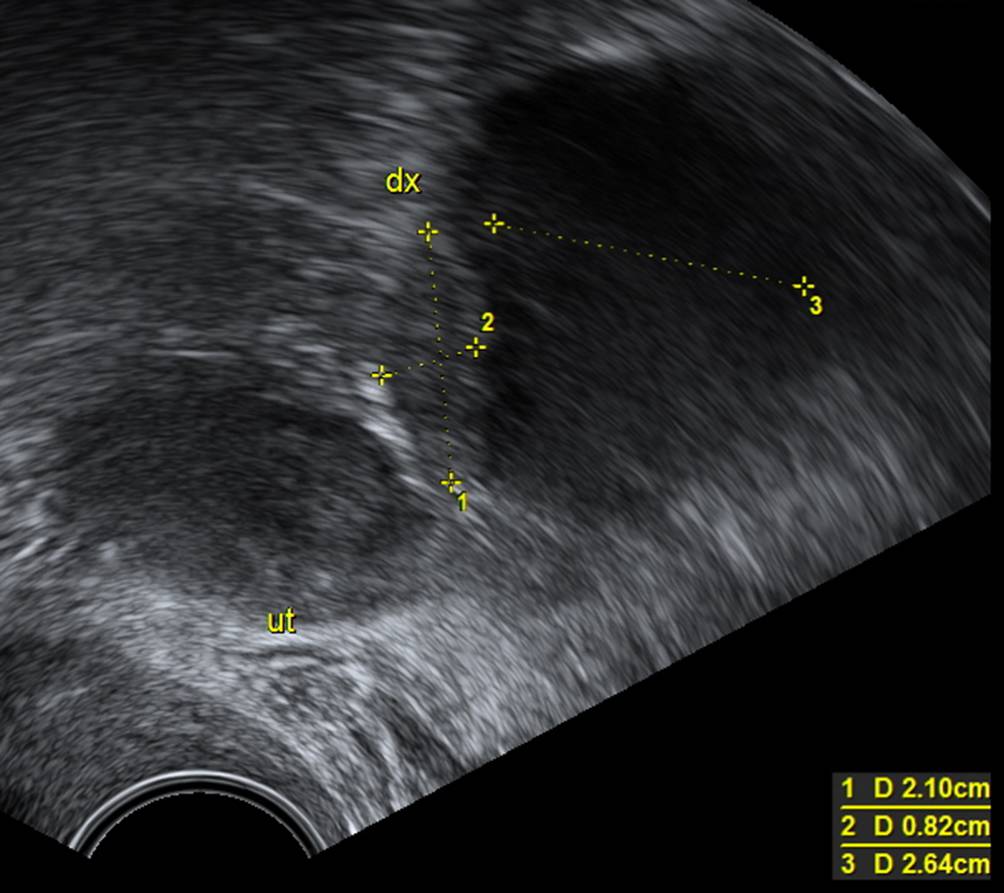

Die „papillary projections“ sind mehr als 3 mm große Vorwölbungen vom Zystenrand ins Zystenlumen (Abb. 6). Die Anzahl dieser Vorwölbungen im Untersuchungsgebiet muss gezählt werden. Sind diese kleiner als 3 mm, so gelten sie als Unregelmäßigkeit der Zystenwand.

Abb. 6

Beispiel für papilläre Projektion. Die gemessene Strecke beträgt 4,4 mm. Es ist wichtig, nur die papilläre Projektion zu messen und nicht auch den Zystenrand